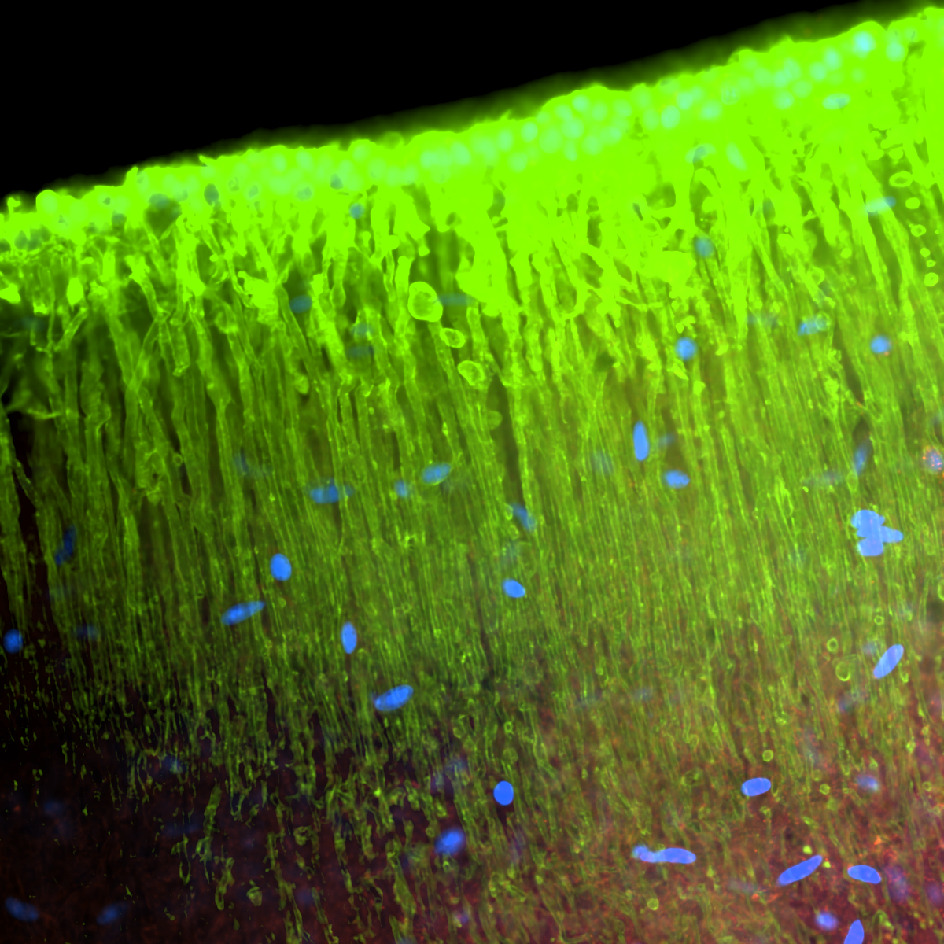

Anejos: fotos Expo “NeuroArte”: Una década revelando ciencia microscópica

Durante estos diez años, el CEN ha sido escenario de importantes avances en biología celular, neurociencia e investigación biomédica. Entre sus logros se destacan producir más de 140 publicaciones científicas en revistas revisadas por pares; la obtención de varios grants competitivos de fondos federales que han allegado millones para proyectos de investigación; apoyo directo a estudiantes graduados en el desarrollo de sus tesis de maestría y doctorado; contribución al desarrollo de patentes científicas por investigadores de la UPR; y la realización de talleres especializados y entrenamientos técnicos para cientos de participantes locales e internacionales.

El Centro de Excelencia Nikon (CEN), cuya casa es el Centro Molecular, desde su fundación ha sido un motor de innovación en microscopía avanzada, posicionando a Puerto Rico como un referente regional en bioimágenes. Esta instalación ha permitido el acceso a tecnología de punta para investigadores y estudiantes, fortaleciendo la capacidad científica local y conectando a la isla con redes internacionales de investigación.

El CEN se ha convertido en un semillero de talento científico, elevando las competencias de estudiantes subgraduados, graduados, postdoctorales y técnicos especializados. Su impacto va más allá del ámbito académico, al atraer proyectos colaborativos, alianzas con la industria biotecnológica y farmacéutica, y fomentar el desarrollo de startups y servicios especializados en la isla.